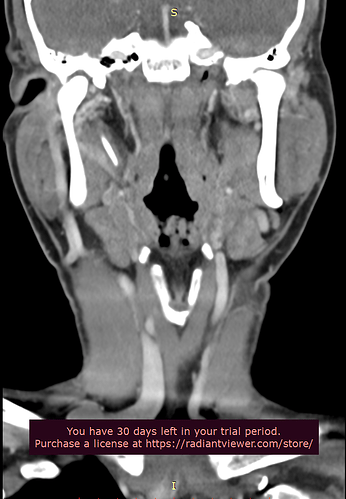

Please do a CT VENOGRAM of the brain and cervical spine with contrast. Please do a 3D reconstruction to show styloids. Please also measure the styloids.

Patient with symptoms of intracranial hypertension (pseudotumor cerebri) compatible with compression of the internal jugular vein at the transverse process of atlas (C1) or styloid process. Please do the scan in neutral.

Please make sure the CT Scan is capture while the contrast is in the internal jugular vein. This patient is suspected of having significant compression of the internal jugular vein(s) between the styloid bone and/or atlas. This is not a CT angiogram order it is a venogram. Surgical decisions will be made based on this scan.